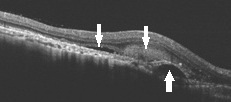

黄斑変性症はフィルムに当たる網膜の機能低下により視力低下や変視症がでる病気ですが、病初期では網膜色素上皮層や脈絡膜(中央写真:白矢印)に病変が生じ、病気の進展に伴いさらに網膜のダメージへと進展してゆくことがほとんどです(右写真:下向き矢印は網膜、上向矢印は脈絡膜の障害)。一見OCT上では強いダメージがあるように見えても良好な視力を維持できている方もいらっしゃれば、その逆の方もいらっしゃいます。なかなか一筋縄ではいかない病気の代表ですが、検査・治療法は確実に進歩しています。

まず黄斑部のOCTの正常像について説明します。上の写真が正常像で、真ん中あたりがへこんでいます。ここが中心窩といって黄斑の中心部です。水色の幅の部分が網膜で黄色の幅の部分が脈絡膜です。その間に網膜色素上皮層があり、2つの膜を隔てています。脈絡膜の深いところには超音波が届かないのですが、この3層がどのようになっているかが重要です。網膜にはいくつかの層構造が見てとれると思いますが、とぎれていたり、乱れていたり、本来無い組織が出てきたりしていると問題になります。